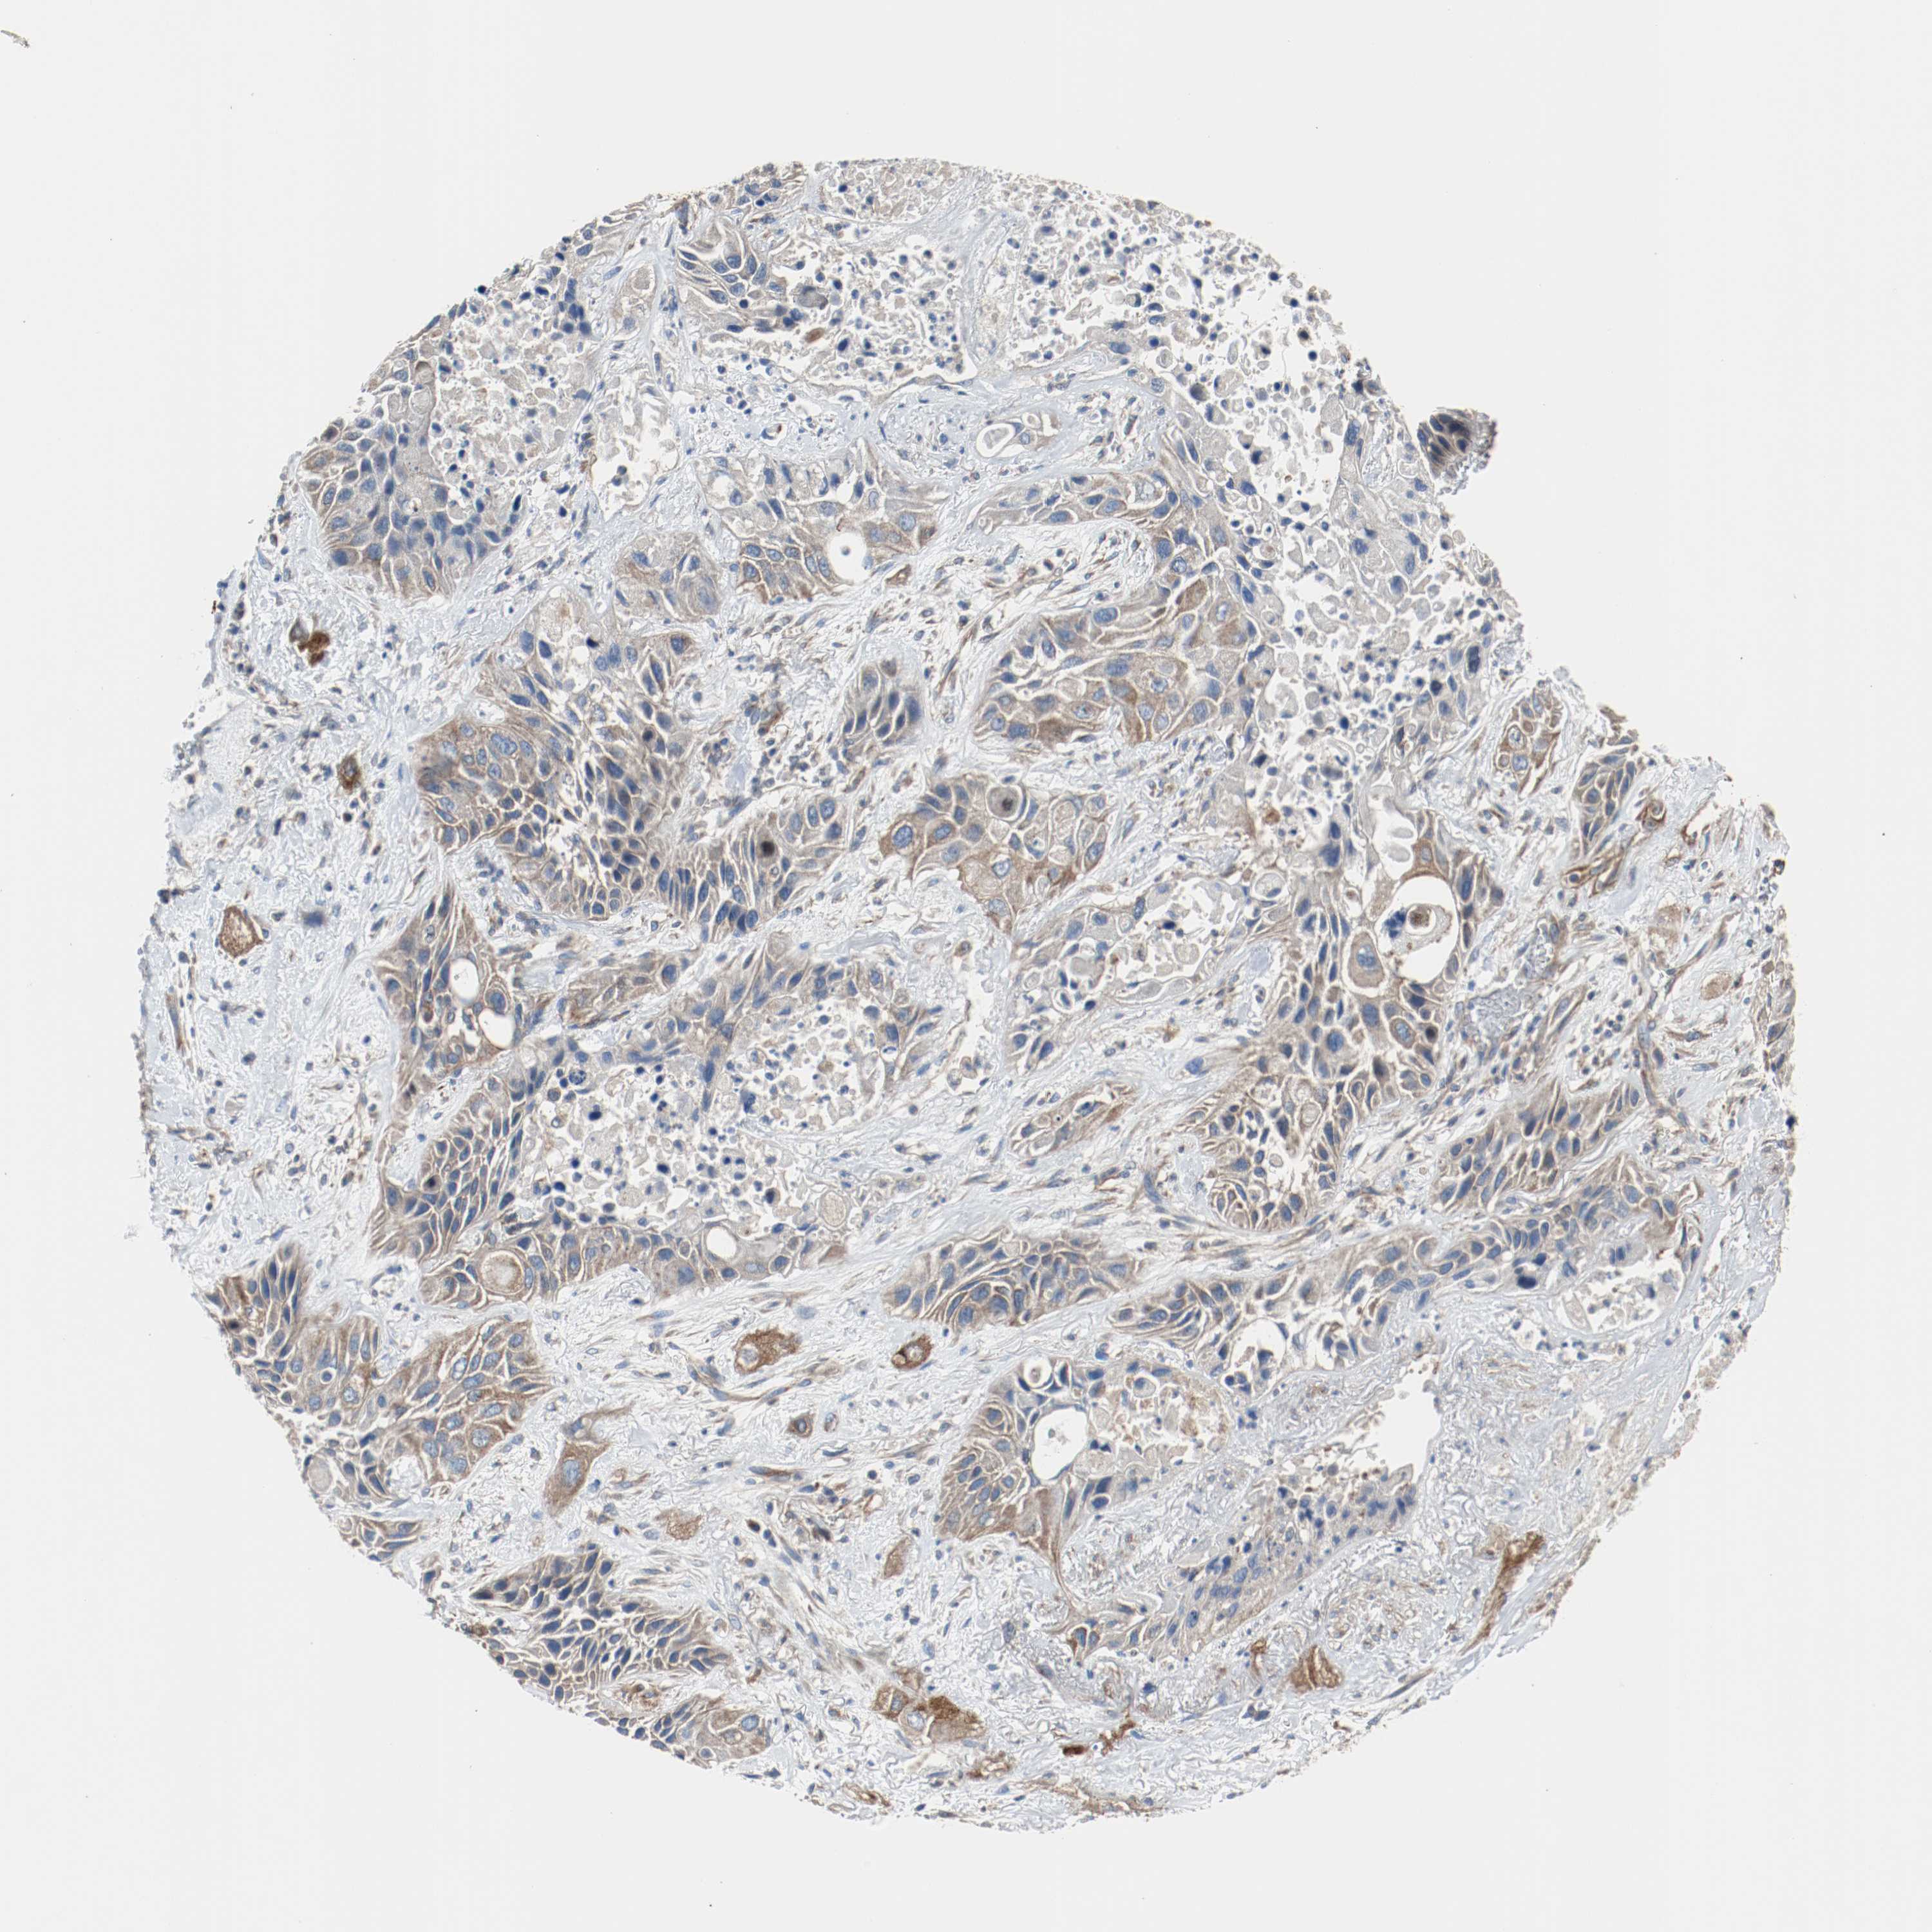

TUBA3D